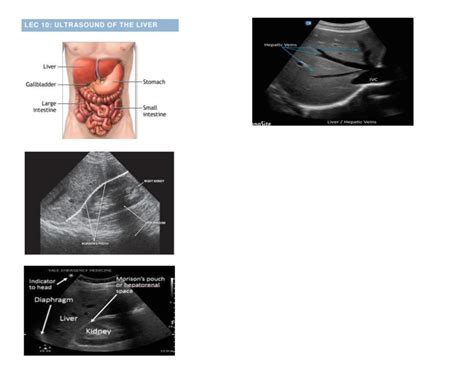

The abdomen normal png is a valuable resource for medical professionals and researchers, offering a detailed visual representation of the abdominal region in its typical, healthy state. This image is an essential tool for understanding the anatomy and structure of the abdomen, which is a complex and vital part of the human body. By examining the normal appearance of the abdomen, medical practitioners can identify any deviations or abnormalities that may indicate potential health issues.

One of the key benefits of using abdomen normal png images is the ability to compare and analyze them with other medical images. This comparison can help healthcare professionals identify subtle changes or anomalies that might be indicative of disease or injury. By having a baseline image of a healthy abdomen, medical experts can more effectively detect and diagnose a range of conditions, from gastrointestinal disorders to liver or kidney issues.